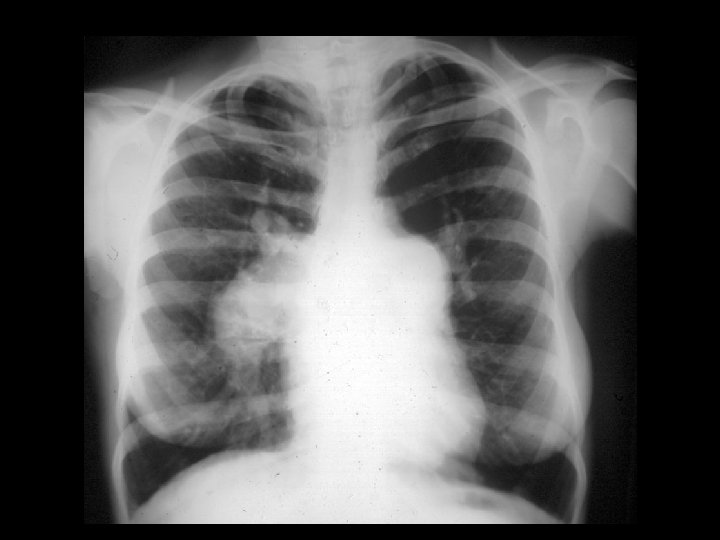

Clínica y diagnóstico o El primer signo de ruptura septal ventricular en post-infarto es la aparición de un soplo pansistólico. Borde esternal inferior izquierdo. RX Tórax: hipertensión venosa pulmonar y aumento del flujo sanguíneo pulmonar.

Clínica y diagnóstico o o El soplo puede ser resultado de una CIV o de insuficiencia mitral, ambas condiciones pueden coexistir. Ecocardiograma (TT o TE): Alta sensibilidad y especificidad, seguro, y rápido.